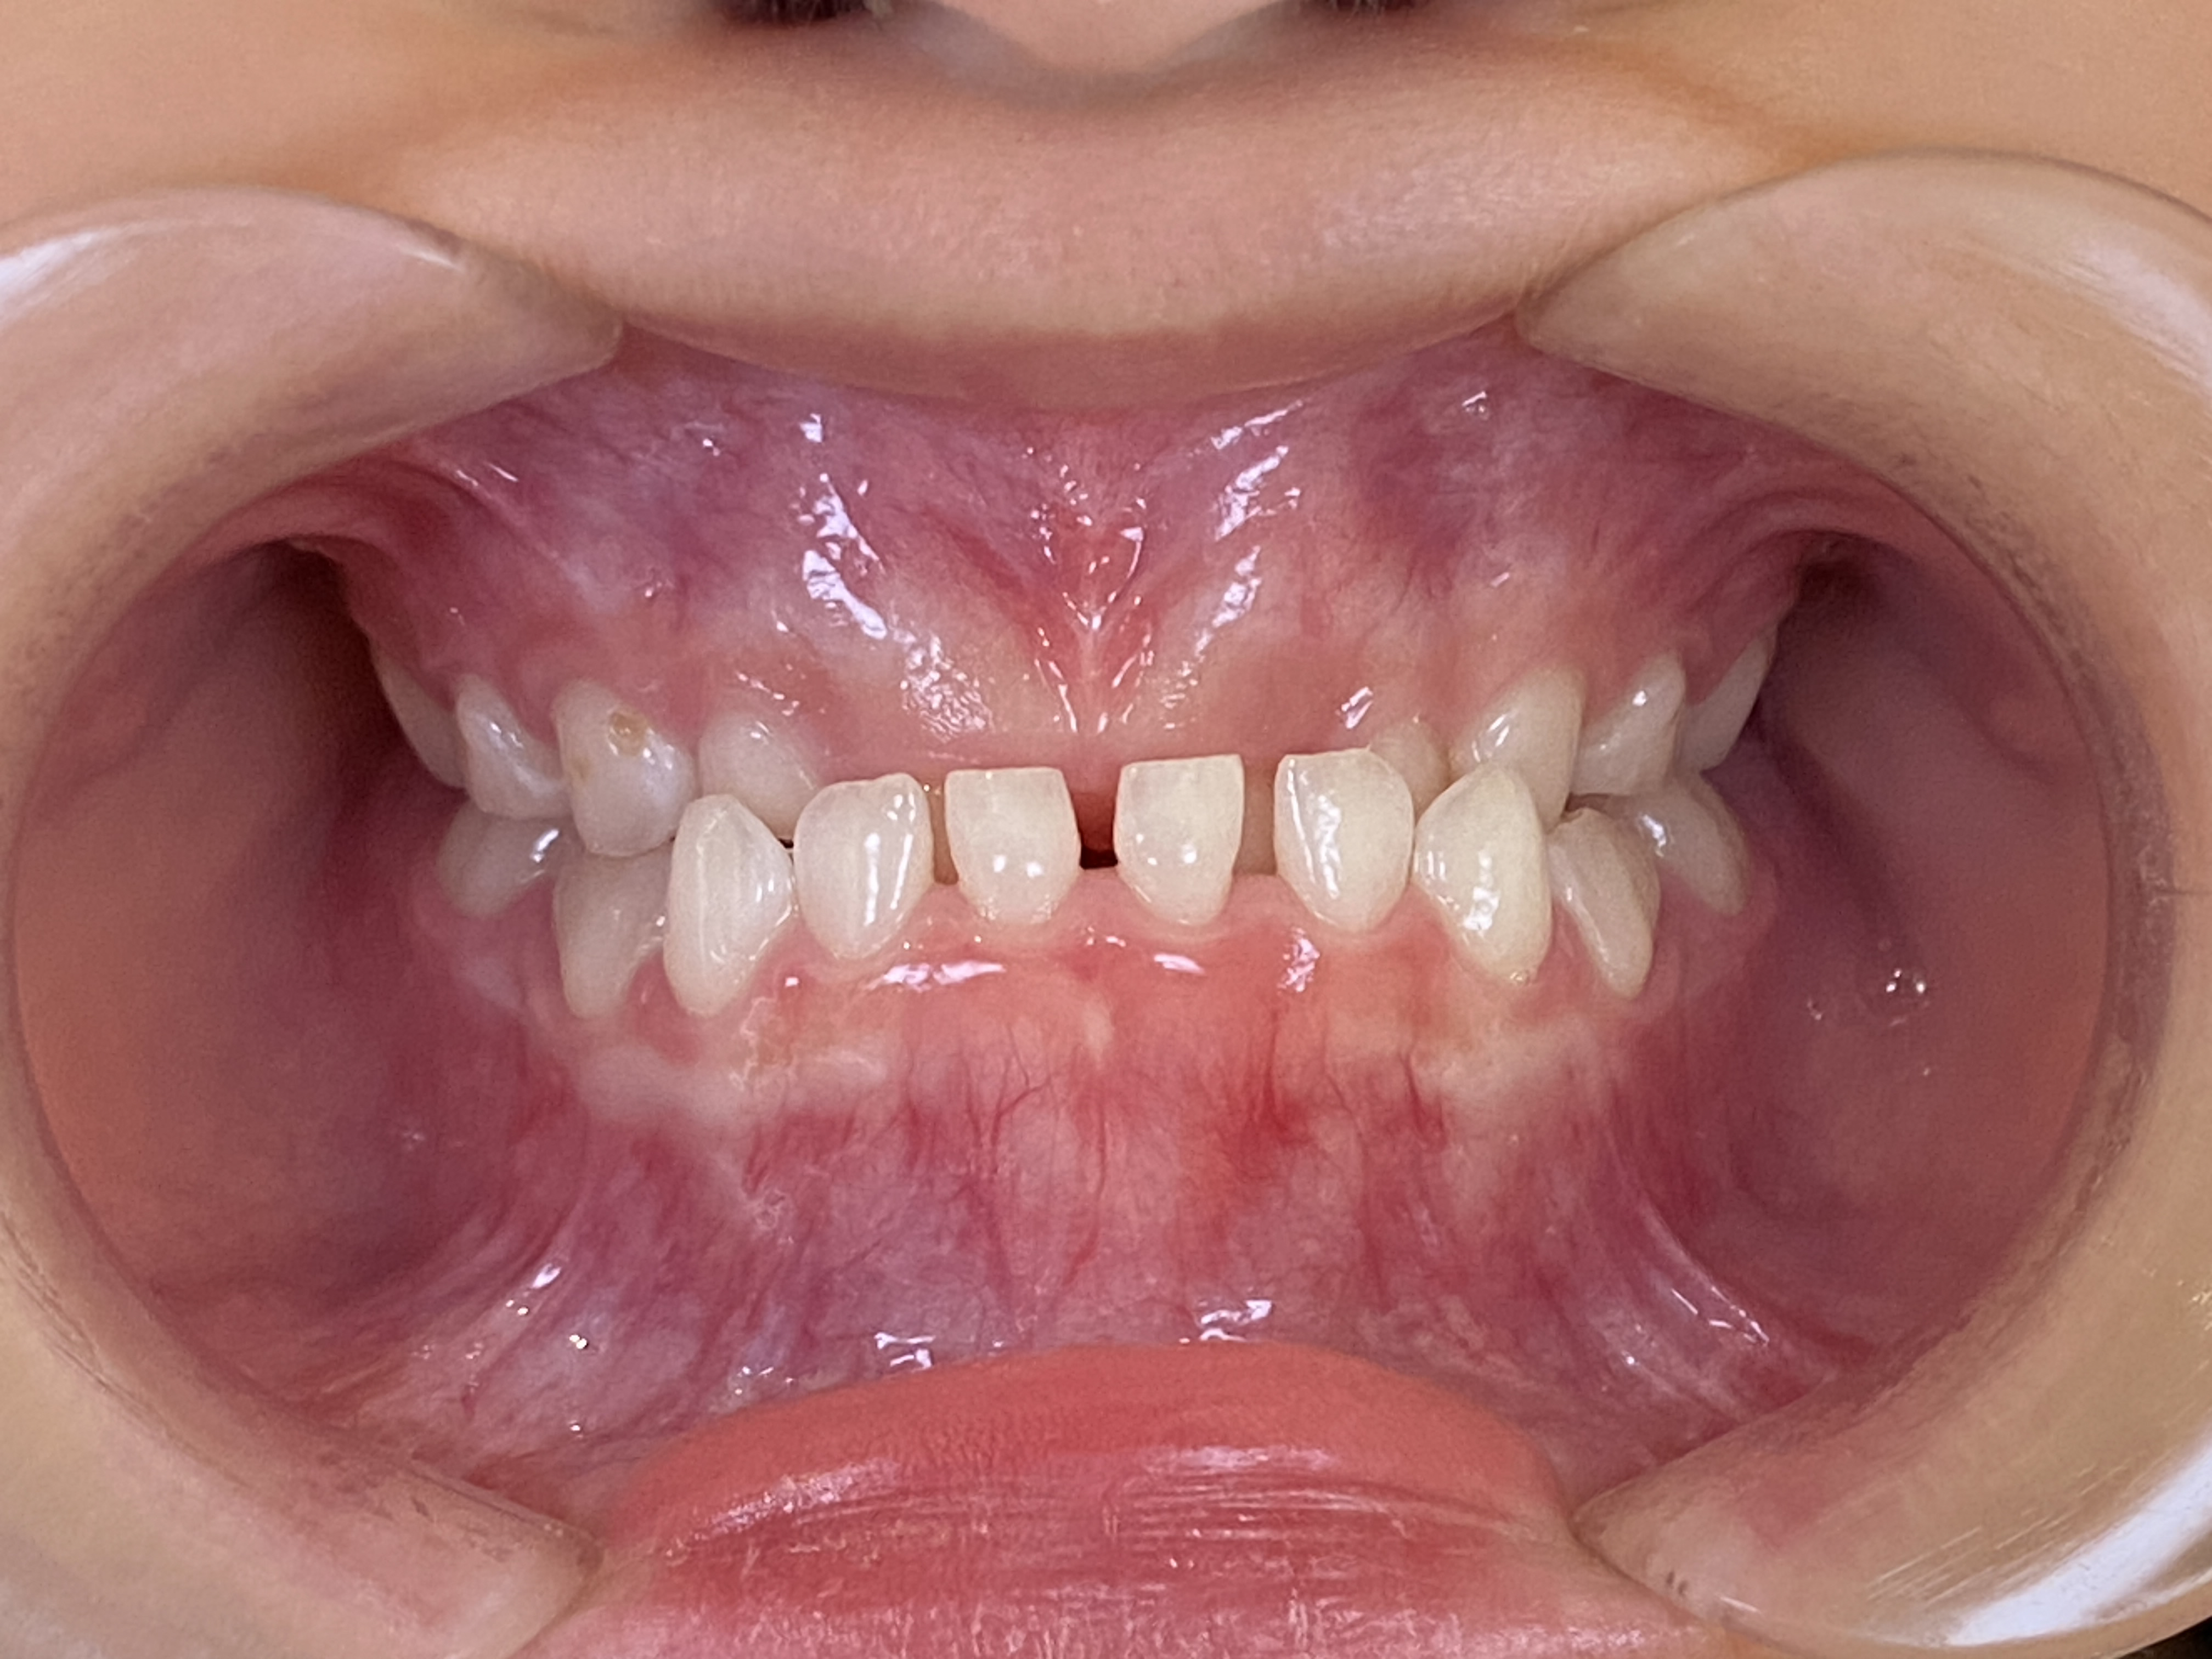

インビザラインファースト症例|上の前歯に隙間があって気になる

2026/02/21 小児矯正